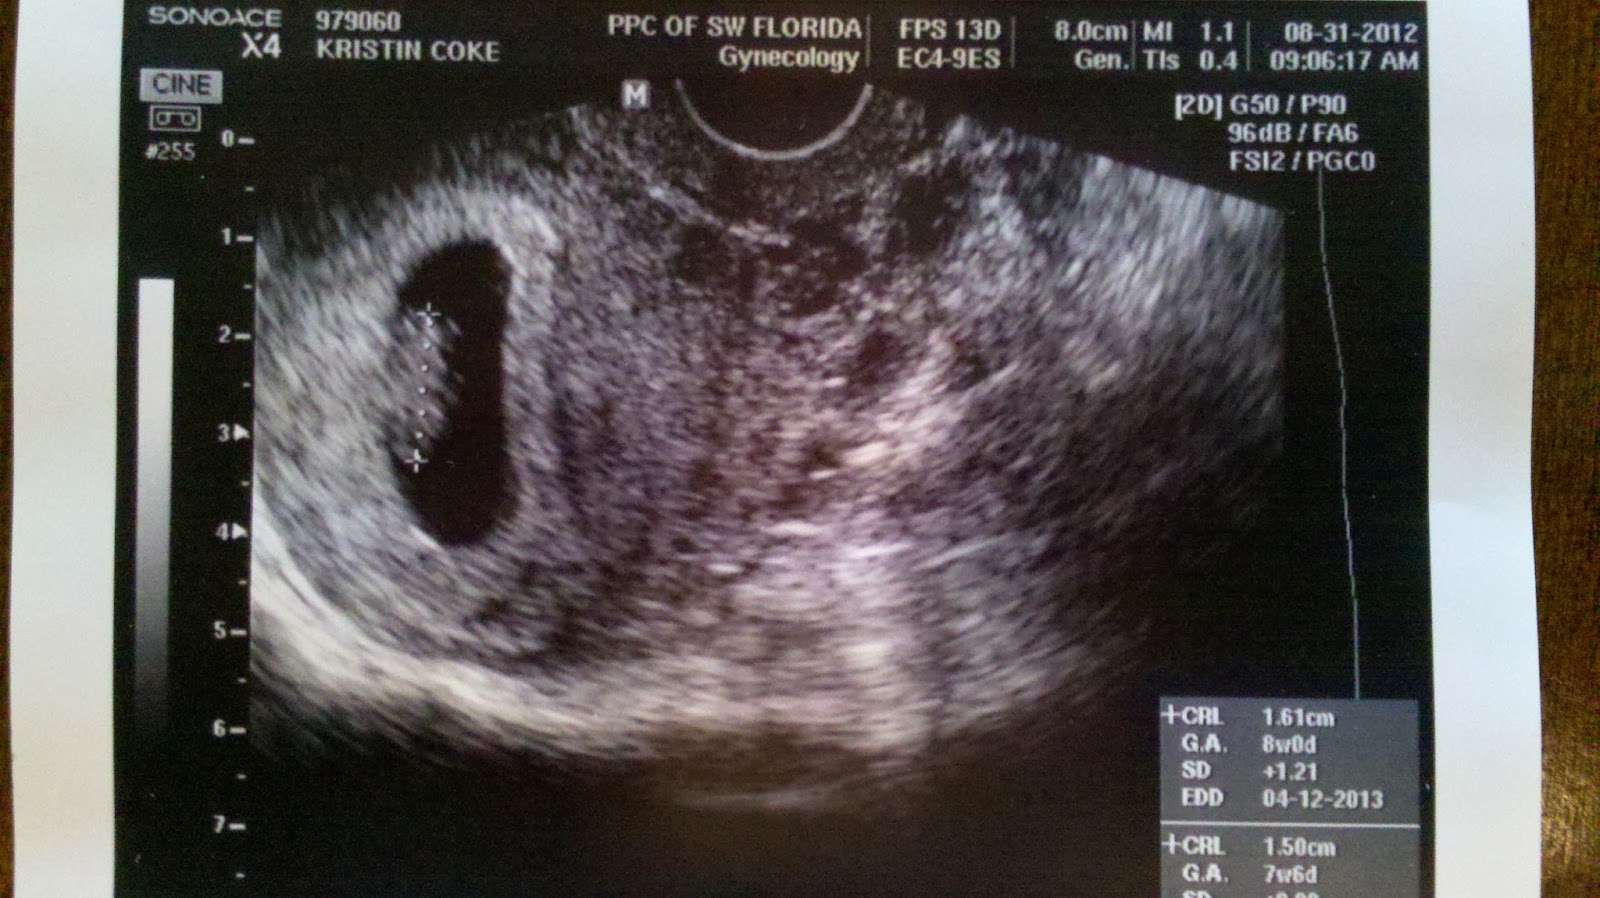

We experienced the most awesome, incredible, amazing, sunshine and rainbows day of our lives when we welcomed Miles Clark to the world. We did not know then the overwhelming love, joy and happiness that would now fill our home. We became parents. It still sounds funny when I say it out loud. Miles does let us know we’re doing an awesome job, though.

I did not think I could love Evan more; then, I saw him as a father, and I found a new love that I didn't know existed. And we both found that it was possible to have an enormous mountain of love for a teeny, tiny person.